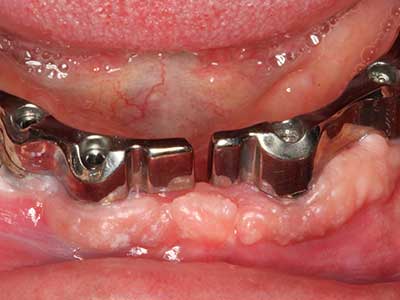

Indikation: Parodontaltherapie

Marginale Parondontalerkrankungen stellen im fortgeschrittenen Alter den Hauptgrund für Extraktionen dar. Sie basieren im Wesentlichen auf einer bakteriellen Besiedlung der Zahnfleischtasche und hierdurch bedingten Entzündung mit konsekutivem Verlust des Zahnhalteapparates. Die Ausbildung subgingivaler Biofilme und Konkremente stellt einen wesentlichen ätiologischen Faktor für den marginalen Knochenabbau dar, so dass ihrer Entfernung eine wesentliche Bedeutung in der Therapie zukommt (Drisko 2014, Plessas 2014).

Zur Behandlung einer marginalen Parodontitis lassen sich eine initiale und chirurgische Therapiephase unterscheiden. Neben der Mundhygieneinstruktion und -motivation sollte in beiden Phasen eine suffiziente Reinigung der Wurzeloberfläche erfolgen, wobei im regenerativen Setting zumeist ein offener Zugang gewählt wird. Die Reinigung der Wurzeloberfläche kann durch die Verwendung spezieller Ansätze auch piezochirurgisch erfolgen, wobei unterschiedlich gebogene Instrumente auch schlecht zugängliche Bereiche wie Furkationen erreichen. Die systemimmanente Wasserkühlung spült dabei die gelösten Konkremente und Bakterien aus der Tasche. Um zusätzlich die Abtragung von Zahnhartsubstanz zu minimieren, wurde bei speziellen Systemen wie dem Piezomed ein Applikations-Feedback eingebaut. Hierbei wird die Abtragungsleistung konsequent reduziert, je mehr Druck auf den Parodontalansatz ausgeübt wird.